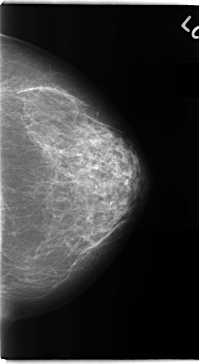

C_0151_1.RIGHT_MLO

C_0151_1.LEFT_MLO

C_0151_1.RIGHT_CC

C_0151_1.LEFT_CC

LEFT_CC LINES 4728 PIXELS_PER_LINE 2584 BITS_PER_PIXEL 12 RESOLUTION 50 NON_OVERLAY

LEFT_MLO LINES 4736 PIXELS_PER_LINE 2584 BITS_PER_PIXEL 12 RESOLUTION 50 NON_OVERLAY

RIGHT_CC LINES 4728 PIXELS_PER_LINE 2664 BITS_PER_PIXEL 12 RESOLUTION 50 OVERLAY

RIGHT_MLO LINES 4736 PIXELS_PER_LINE 2656 BITS_PER_PIXEL 12 RESOLUTION 50 OVERLAY

LESION_TYPE CALCIFICATION TYPE PLEOMORPHIC DISTRIBUTION CLUSTERED

ASSESSMENT 4

SUBTLETY 3

PATHOLOGY MALIGNANT